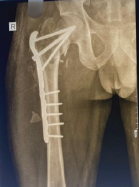

Case 7

A 60-year-old female with osteoporosis sustained a displaced Garden’s type IV, Pauwel’s type III fracture. The fracture was fixed in neutral position with the FNS device, but the bolt and anti-rotation screw were placed too anteriorly, leaving a superolateral void at the head–neck junction. Although union was achieved at 5 months, the fracture underwent varus collapse and significant neck shortening, with radiographs showing a widening gap between the plate and lateral femoral cortex compared to immediate post-operative images (Fig. 6). This case emphasizes the importance of central implant positioning and valgus fixation in osteoporotic bone and perhaps a lower threshold for choosing replacement over fixation in osteoporotic bone.

Figure 6 Top left: Pre-operative radiographs of Case 7; top center: immediate post-operative AP radiograph of the fracture; top right: union with a shortened neck and varus collapse. Bottom left: Pre-operative radiograph of Case 8; bottom center: Intraoperative C-arm images following reduction to neutral- clearly showing a supero-lateral bony void; bottom right: varus collapse and neck shortening noticed at 7 months.